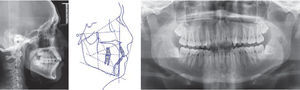

De acuerdo al análisis de los estudios cefalométricos, éstos determinan que sus porciones maxilares son adecuadas y presenta una clase I esquelética, crecimiento neutro, así como proinclinación y protrusión dentoalveolar.

La radiografía panorámica revela la presencia de terceros molares superiores e inferiores incluidos, así como la relación corona-raíz 1:2 de los 28 órganos dentarios erupcionados y con función, no se observan patologías aparentes (Figura 3).